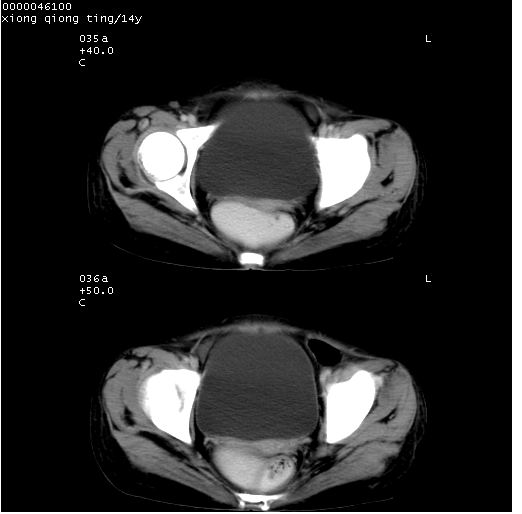

患儿 女,14岁。不规则发热一周,偶感头痛,无抽搐及呕吐。pe:神清,精神差,双侧瞳孔等大等圆,对光反射敏感,双肺未闻及明显啰音,心音有力,腹部触之似揉面感,下腹压痛,无反跳痛。

腹部b超提示:子宫缩小,盆腔积液,肝实质回声密集。

临床诊断:发热原因待查:1)腹部结核感染。2)伤寒?3)结缔组织病?

中下腹及盆腔ct轴位平扫+增强扫描(层厚10mm,螺距1.0,重建间隔10mm),图像如下:

(注:患儿检查当日上午9时口服胃肠道对比剂,下午3时许行ct扫描检查,未行对比剂直肠保留灌肠,检查当日患儿腹泻)

中下腹及盆腔ct轴位扫描(ps+ce)提示:腹部肠管明显充气扩张,并见数个不同宽度之气液平面;疑不全性肠梗阻或肠郁张。临床会诊考虑为患儿腹泻,肠郁张所致;后来未经特殊处理,患儿大便恢复正常,亦无腹胀。

临床出院诊断:1)结核性腹膜炎。2)腹膜后淋巴结结核。3)脂肪肝。